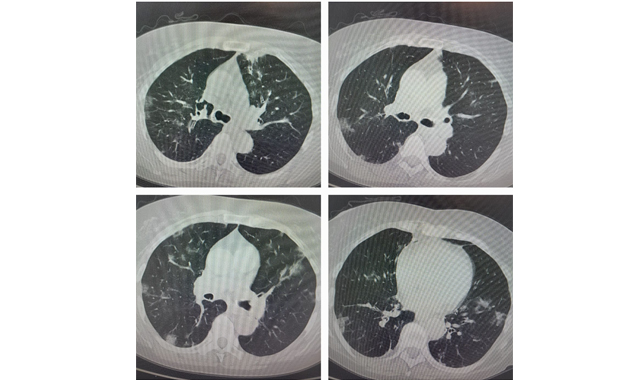

Halkın hastalığı öğrendiğini ve artık panik yapmadığını ifade eden Prof. Dr. Şevket Özkaya, "Gençlerde grip gibi seyrettiği için COVID-19 testine gerek yok ve semptomatik ilaçlar ile tedavi yeterli iken, özellikle uzamış öksürük ve yaşlı hastalarda akciğer tutulumu açısından doktora görüşmeleri ve akciğer için film çekilmesini öneriyoruz. Hastalarda bu seferki en fazla şikayet özellikle baş ağrısı ön planda. Son günlerde test pozitif hastalarda artış olabilir ama ciddi hastalık beklemiyoruz" şeklinde konuştu.